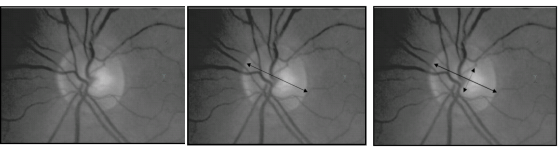

El disco óptico tiene una forma ovalada (mayor diámetro vertical que horizontal) de unos 1.5 mm y es de color amarillento-anaranjado. En su interior se encuentra una depresión o excavación fisiológica que ocupa aproximadamente el 30-40% de la papila óptica y que se denomina copa óptica o cup (Figura 2 y 3). La relación copa/disco (cup/disc) es por tanto en torno al 0.3-0.4.